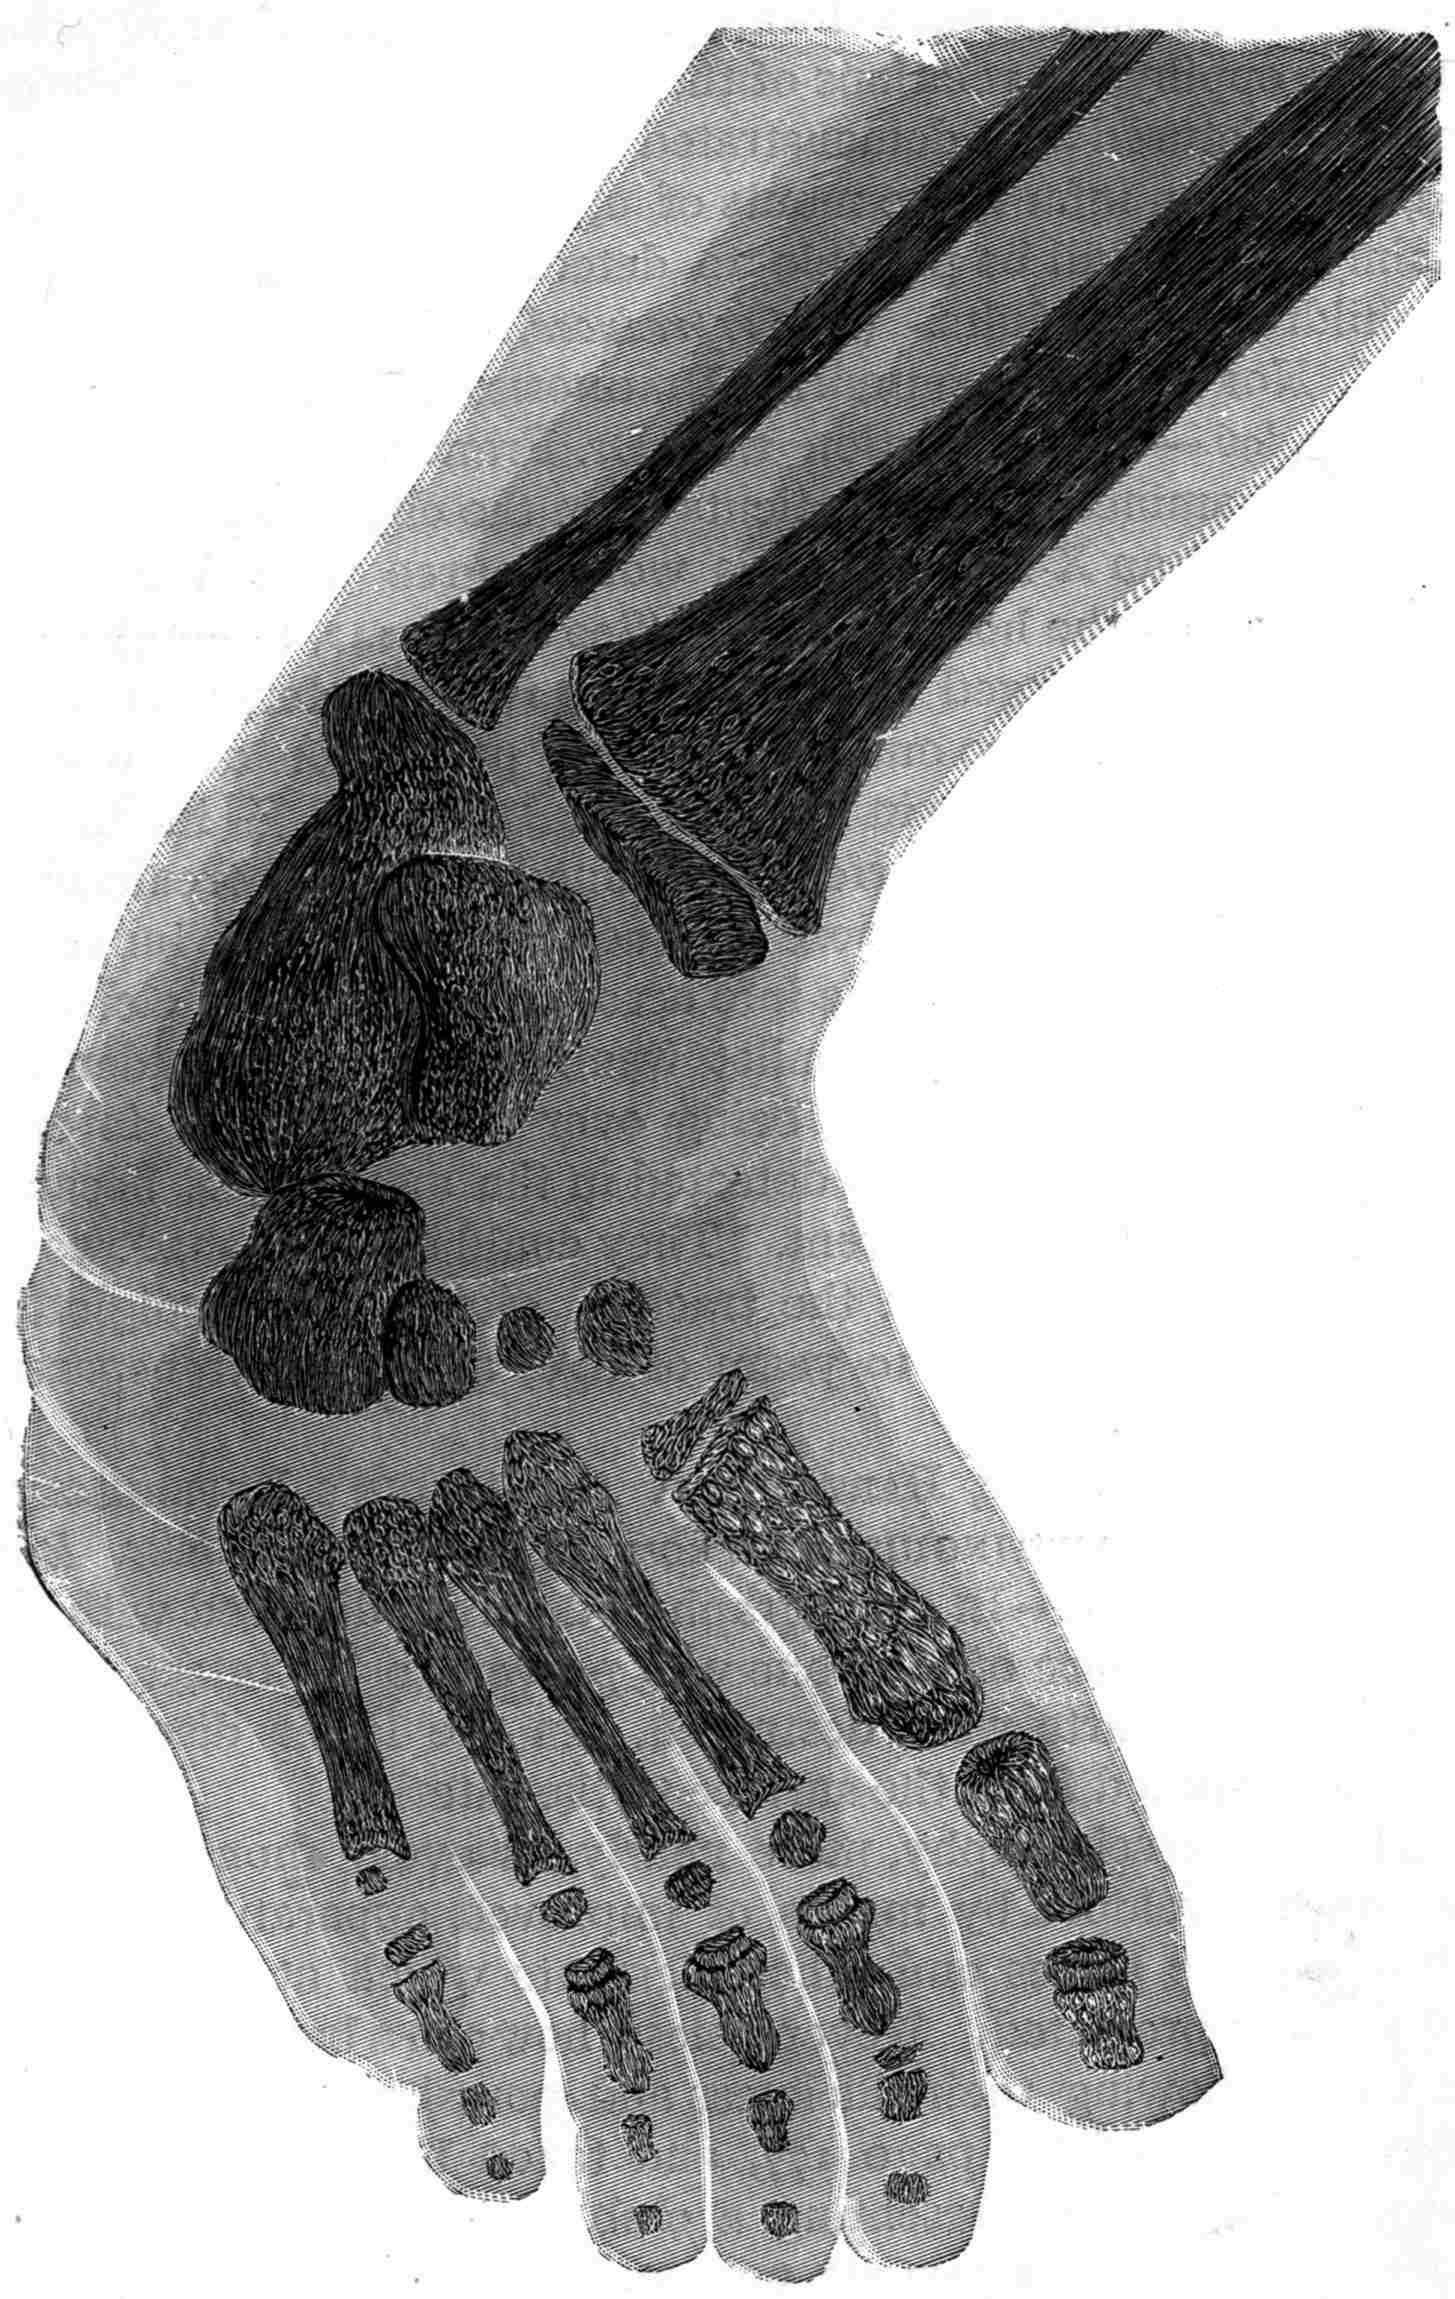

Fig. 2.—Broken Arm, Overlapping.

Fig. 3.—Ribs.

Fig. 4.—Knee, Knickerbocker Buttons, Bullet in Femur.

FROM SCIAGRAPHS BY PROF. DAYTON C. MILLER. § 204.